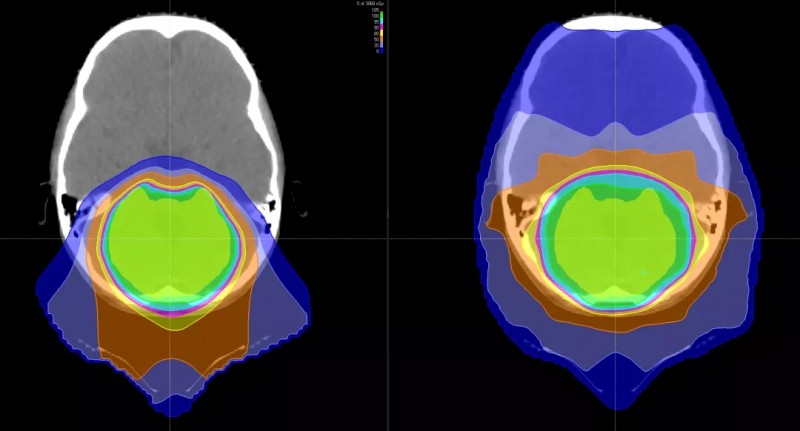

使用质子(左)与X射线治疗(右) 质子治疗对周围重要器官损伤更少

与传统形式的辐射相比,质子束会到达肿瘤内部的精准位置而不是沿着光束离开人体的路径释放大部分辐射剂量。实际上,质子没有肿瘤之外的辐射“退出剂量”,这意味着质子停在肿瘤上,不会继续伤害身体的健康部位。